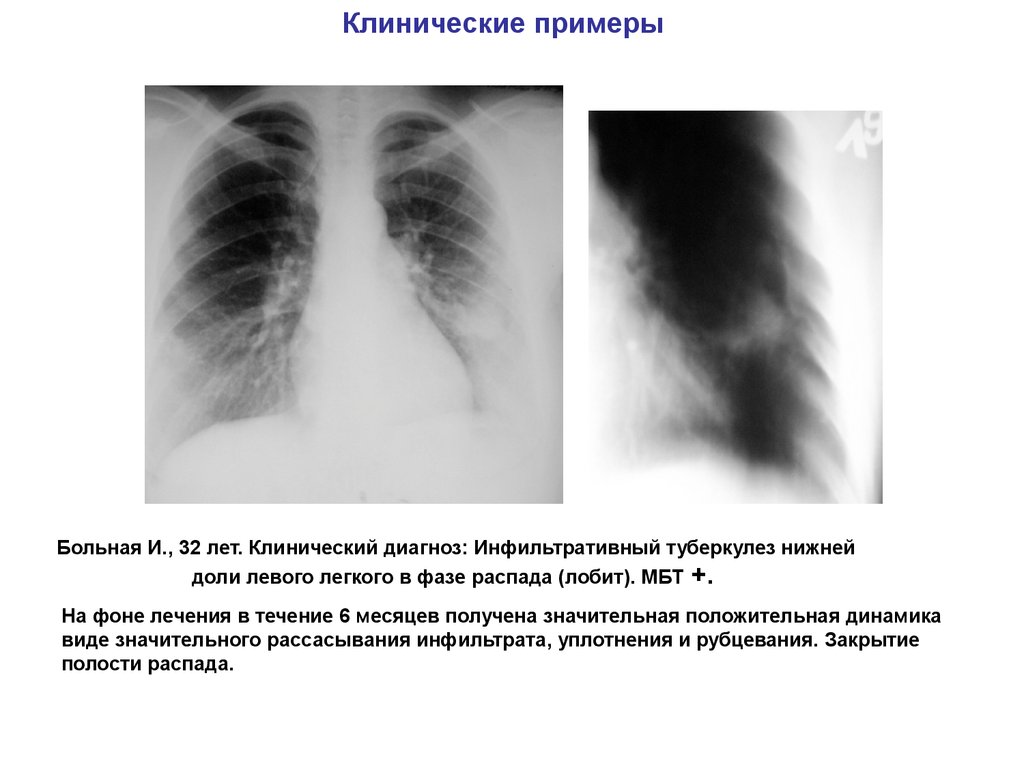

Иллюстрации по теме очагового и инфильтративного туберкулеза